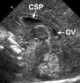

The cave of septum pellucidum (CSP), cavum septi pellucidi, or cavity of septum pellucidum, is a slit-like space in the septum pellucidum that is present in fetuses but usually fuses during infancy. The septum pellucidum is a laminated thin translucent vertical membrane in the midline of the brain separating the anterior horns of the right and left ventricles. [Source: Wikipedia ]